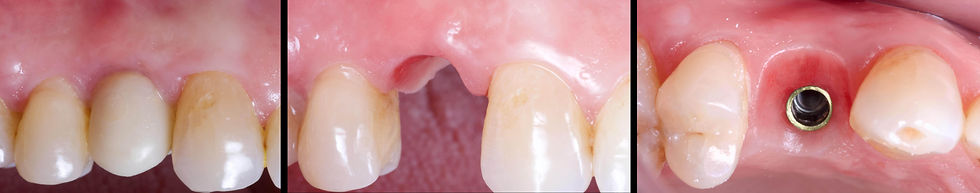

Frontal, lateral and occlusal views of the atrophic area. GO TO THE VIDEO